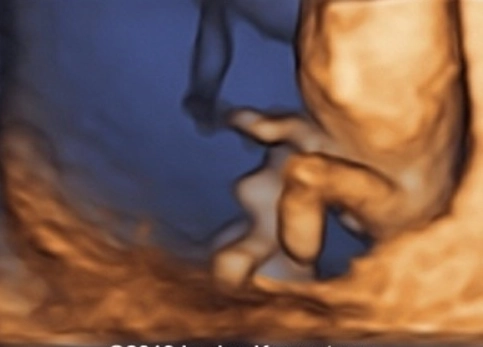

Cứng đa khớp bẩm sinh (Arthrogryposis Multiplex Congenita - AMC)/Chuỗi biến dạng do thai nhi bất động/giảm động (Fetal Akinesia/Hypokinesia Deformation Sequence - FA(H)DS)